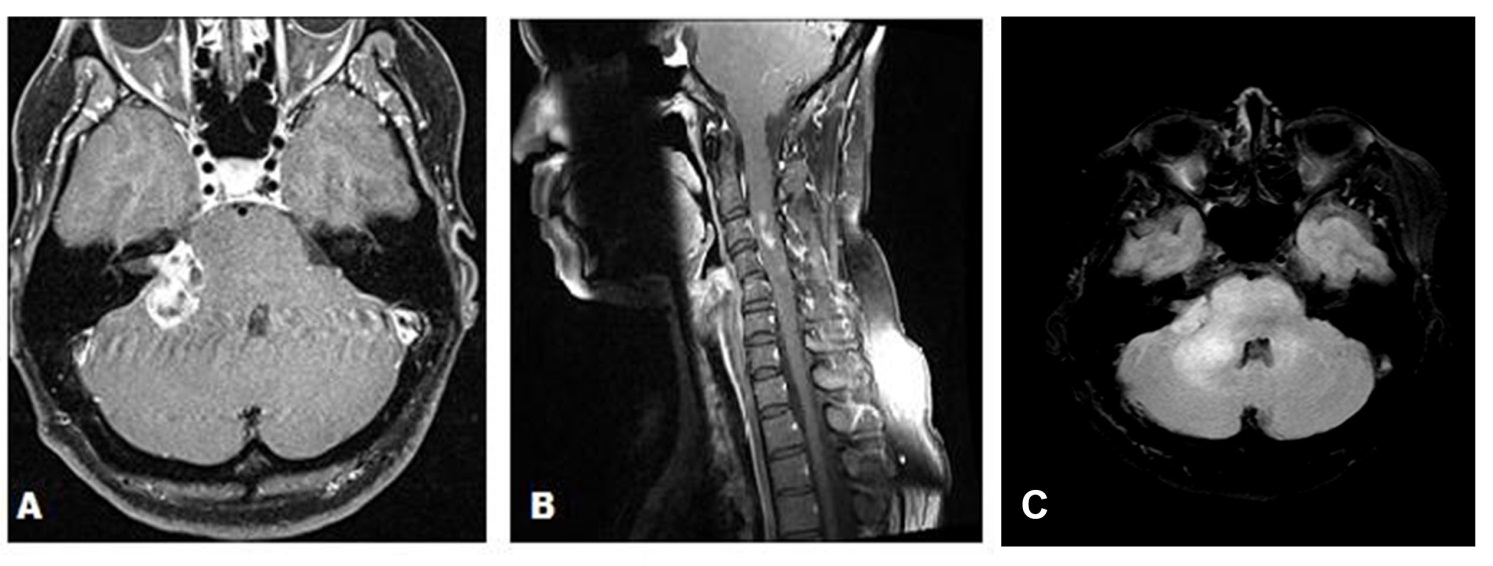

A 43-year-old female presented with a 3-month history of hearing loss in the right ear. A brain MRI in December 2015 showed a right CPA mass deemed to be acoustic neuroma and an expansile cervical spinal cord mass of unknown origin. She did not receive contrast at the time due to her pregnancy. She was lost to follow up and presented in December 2016 with dizziness and bilateral hand numbness that led to a repeat brain MRI with contrast, which showed progression of the brain tumor and areas of enhancement at the C3-C4 levels. (Figure 1). She underwent subtotal resection of the right CPA mass in January 2017 as a gross total resection was deemed unsafe by her surgeon. (Figure 2). Pathology demonstrated the lesion to be a GBM (IDH wild-type, MGMT promoter unmethylated, and absent H3 K27M mutation). The cervical spinal cord lesion was not amenable to biopsy due to the location. After resection, she had further neurological worsening. Neurologic exam showed dysarthria, decreased right hearing, hypotonia of the right arm, bilateral hip flexor weakness, right appendicular dysmetria, upper motor neuron signs on the right, and a wide-based ataxic gait. She received proton beam therapy to both the CP angle mass and the cervical spine mass, as the cervical spine mass was also treated as if it were GBM. She received 60 Gy to the brain tumor in 30 fractions and 50.4 Gy to the spinal cord tumor in 30 fractions with proton beam therapy. She received concurrent Temozolomide at 75 mg/m2 during the 30 fractions of proton beam XRT. Post radiation MRI of the brain and spine showed decreased size of the enhancing right CPA mass; however, there was increased size of the enhancing, expansile mass in the cervical cord extending from C2 to C7 (Figure 3). She initially deferred adjuvant monthly Temozolomide, opting for a holistic approach instead.

Figure 1 (A) Axial gadolinium enhanced brain MRI demonstrating a right cerebellopontine angle mass in December 2016 prior to surgical resection. (B) Sagittal MRI of the Cervical spine with gadolinium in December 2016 demonstrating areas of enhancement at the C3 C4 levels. (C) Axial T2/FLAIR demonstrating extensive edema in the right cerebellopontine angle extending into the brainstem and the cerebellum.